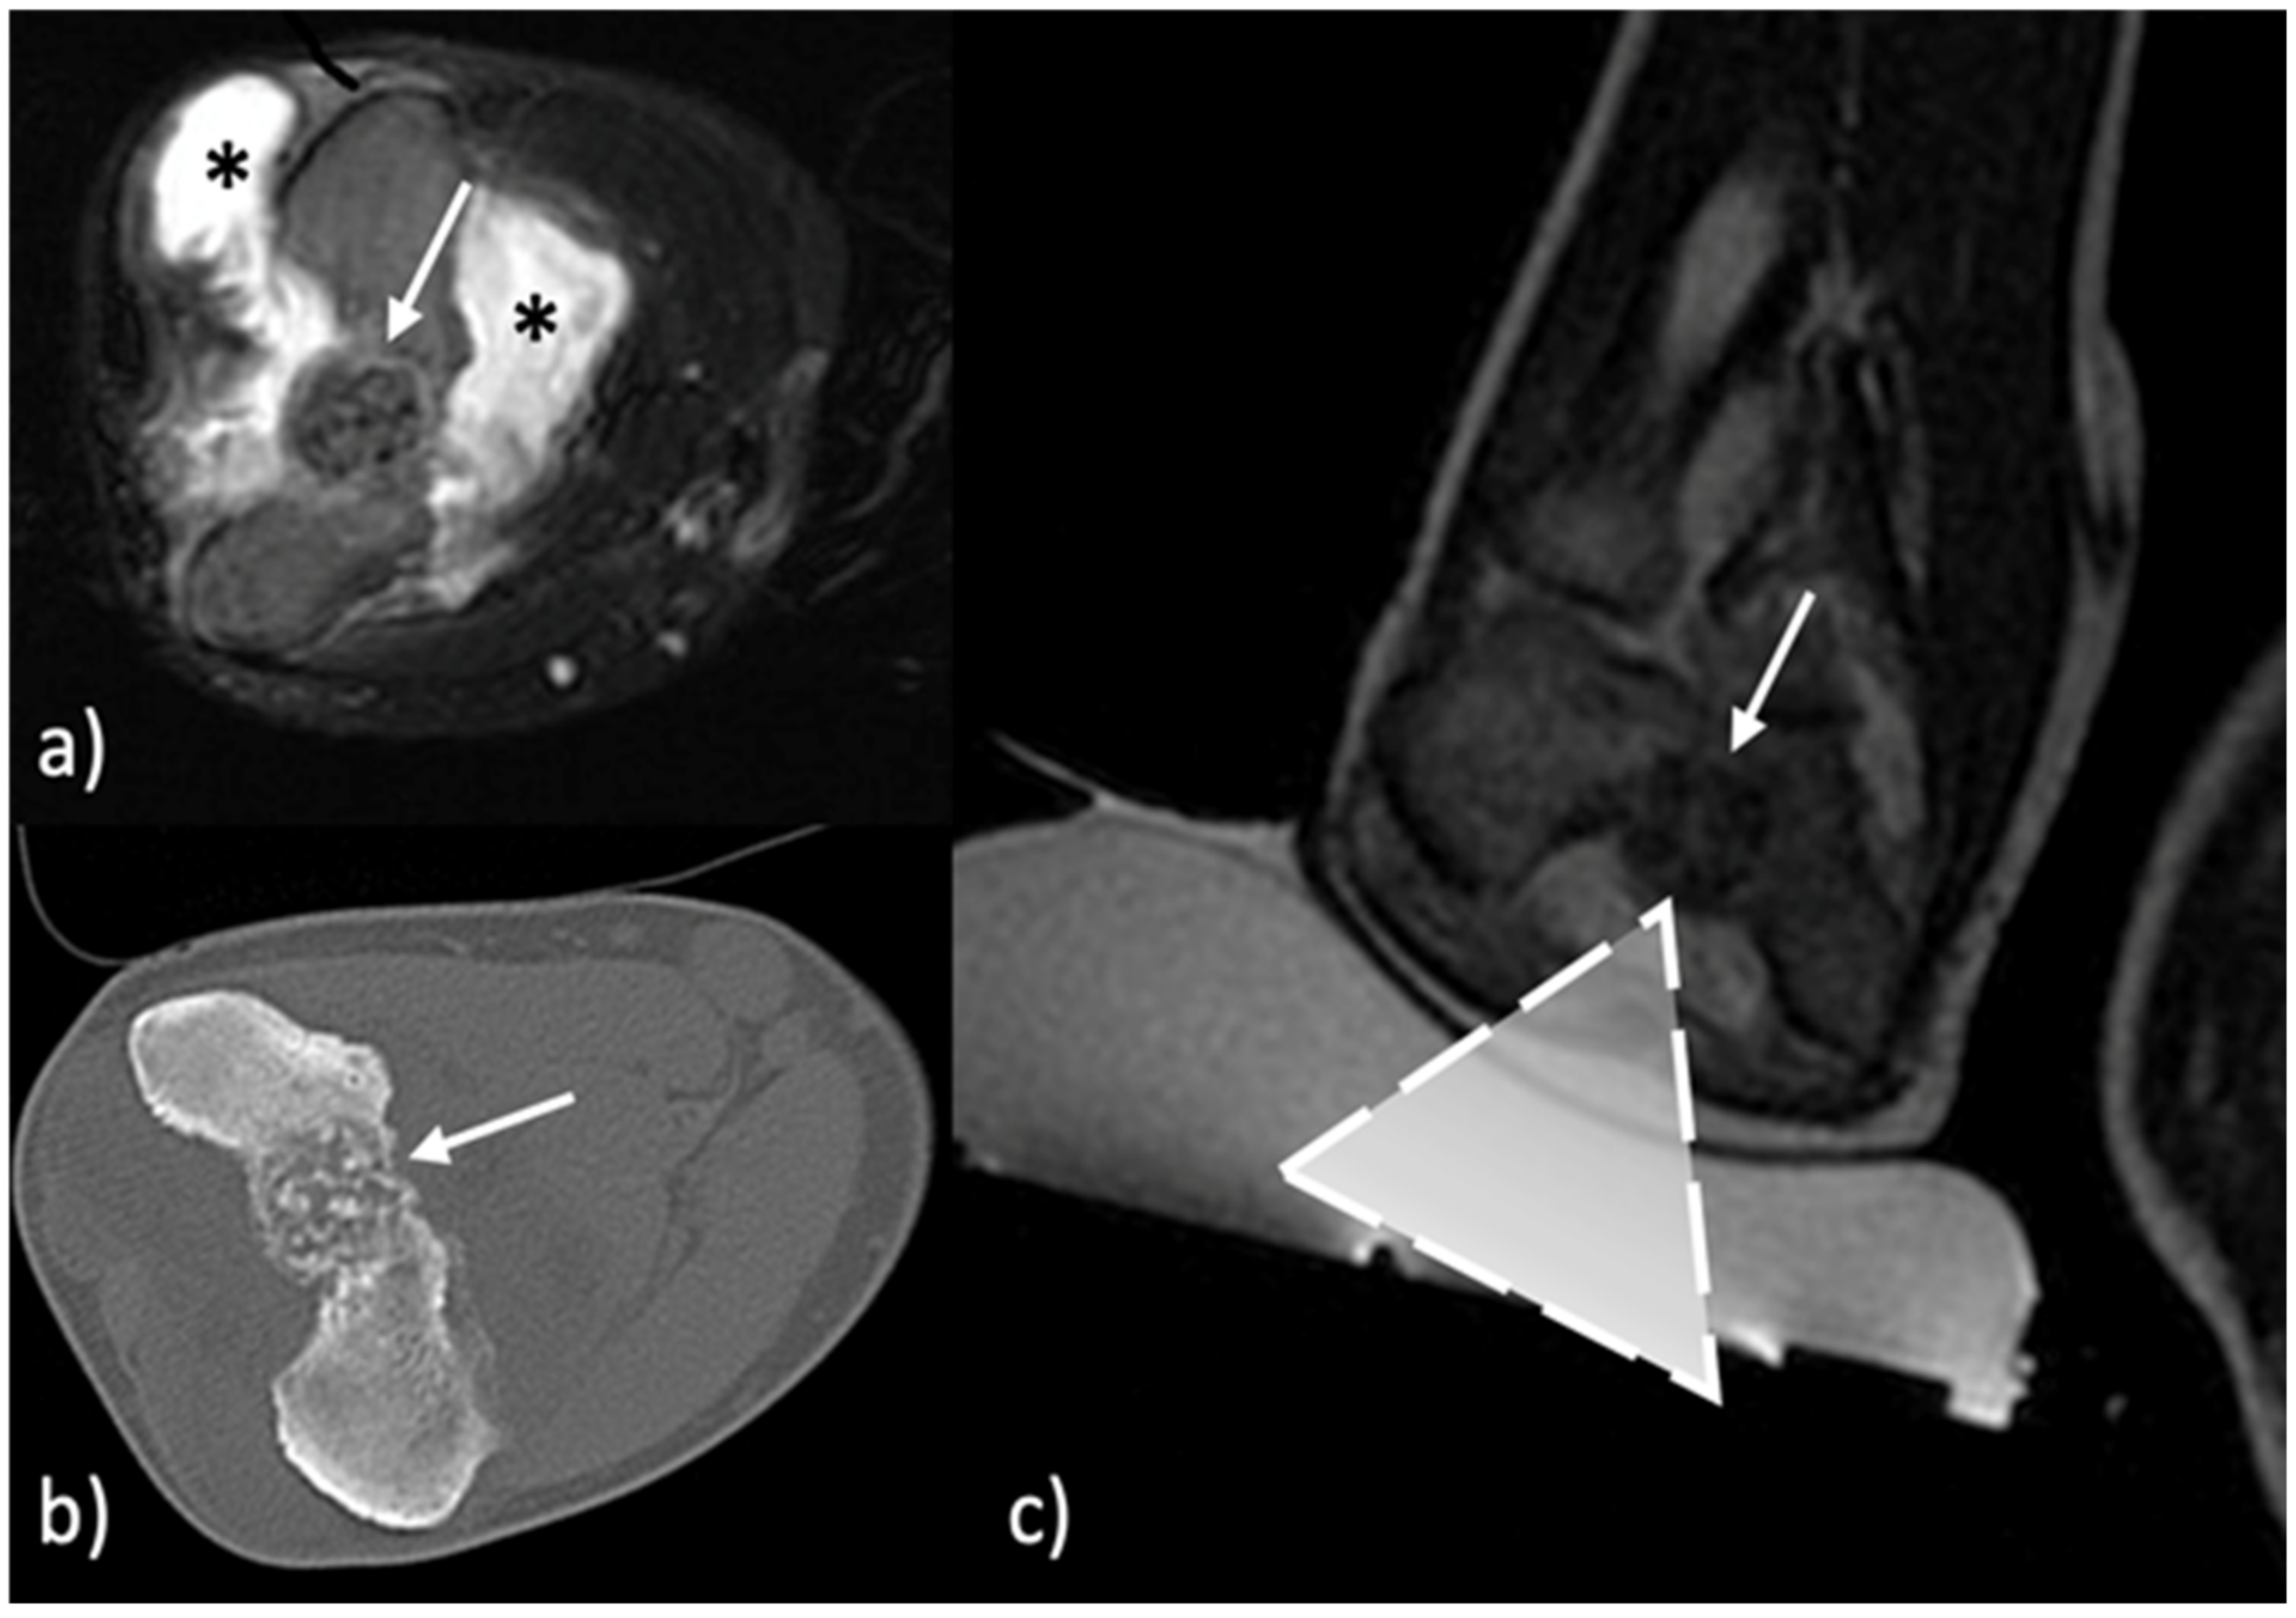

- Arrigoni, F.; Bruno, F.; Palumbo, P.; Zugaro, L.; Zoccali, C.; Barile, A.; Masciocchi, C. Magnetic resonance-guided focused ultrasound surgery treatment of non-spinal intra-articular osteoblastoma: Feasibility, safety, and outcomes in a single-center retrospective analysis. Int. J. Hyperth. 2019, 36, 767–774. [Google Scholar] [CrossRef] [PubMed]